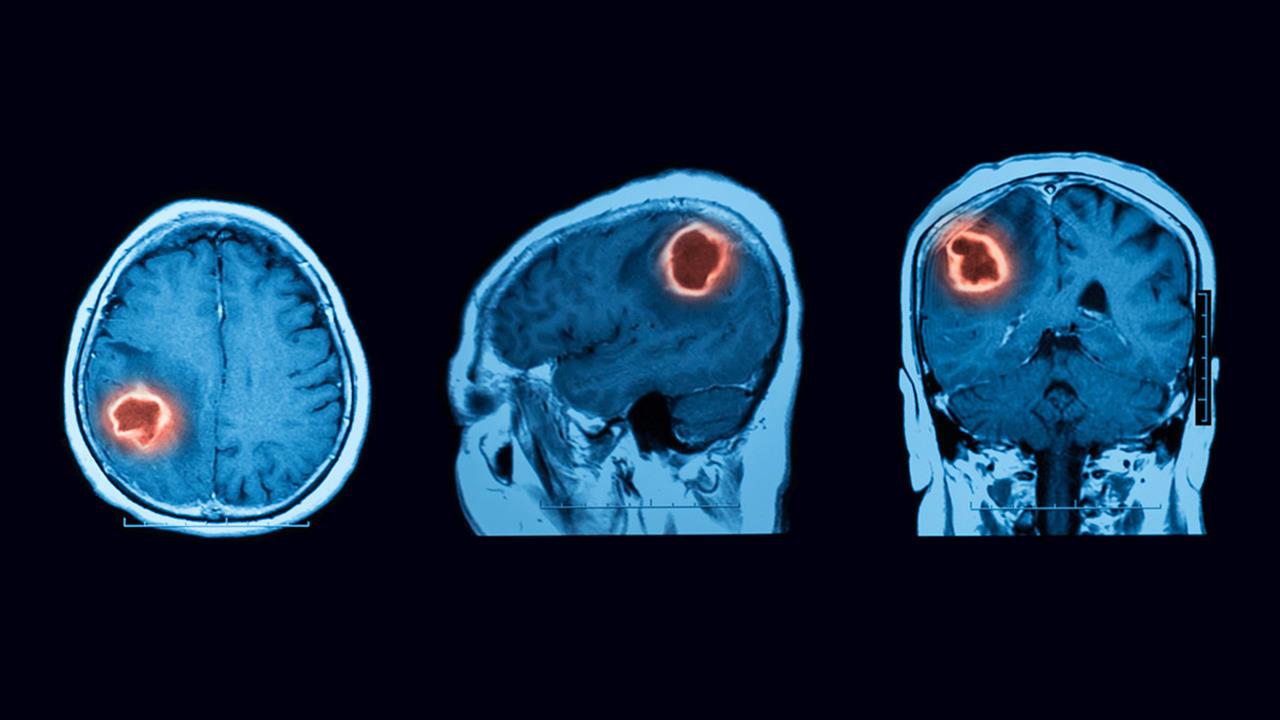

Οι συνέπειες μιας μακροχρόνιας υψηλής αρτηριακής πίεσης είναι επίσης ορατές στην απεικόνιση μαγνητικού συντονισμού (MRI). Οι ακτινολόγοι είναι εξοικειωμένοι με τις "υπερπυκνώσεις της λευκής ουσίας" στη λευκή ουσία του εγκεφάλου, αλλά αυτές είναι μόνο ένα πρόχειρο μέτρο. Σε μεγάλες μελέτες κοόρτης, η υπέρταση σχετίζεται με άλλες λεπτές αλλαγές.

Οι ερευνητές διαπίστωσαν ότι η αυξημένη αρτηριακή πίεση σε 9 περιοχές του εγκεφάλου οδήγησε σε αλλαγές στη μαγνητική τομογραφία που σχετίζονταν επίσης με χειρότερη γνωστική λειτουργία. Αυτές περιελάμβαναν το putamen, το οποίο βρίσκεται στη βάση του εγκεφάλου και είναι υπεύθυνο για τη ρύθμιση της κίνησης αλλά επηρεάζει επίσης και την ικανότητα μάθησης.

Άλλες περιοχές που επηρεάστηκαν, περιελάμβαναν την πρόσθια θαλαμική ακτινοβολία (radiatio thalami), η οποία δημιουργεί συνδέσεις με τον ισόπλευρο εγκεφαλικό φλοιό. Δεύτερον, η corona radiata, μια ευρεία ομάδα νευρικών ινών που συνδέει βαθύτερα τμήματα του εγκεφάλου με τον φλοιό σαν φωτοστέφανο ακτίνων. Επίσης, εμπλέκεται το πρόσθιο τμήμα της capsula interna, το οποίο επίσης τραβά προς τον φλοιό.

Η πρόσθια θαλαμική ακτινοβολία εμπλέκεται και συμμετέχει σε εκτελεστικές λειτουργίες, όπως ο σχεδιασμός απλών και σύνθετων καθημερινών εργασιών, ενώ οι άλλες δύο περιοχές επηρεάζουν τη λήψη αποφάσεων και τη διαχείριση των συναισθημάτων.

Οι αλλαγές στις εικόνες της μαγνητικής τομογραφίας συσχετίστηκαν με τα αποτελέσματα στα γνωστικά τεστ, πράγμα που υπογραμμίζει ρητώς τη συνάφεια. Έτσι, θα μπορούσε να ισχύει το εξής, ότι η μακροχρόνια μη θεραπευόμενη υπέρταση βλάπτει περιοχές του εγκεφάλου που χρειάζονται οι άνθρωποι για γνωστικά καθήκοντα.